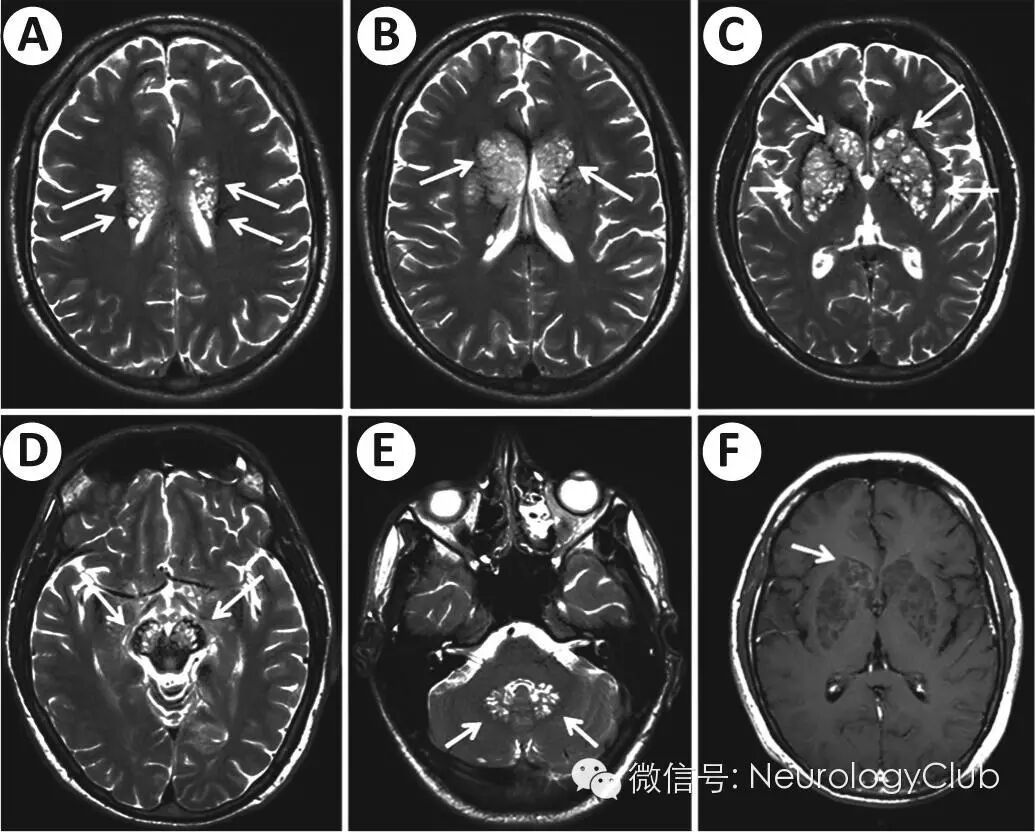

24岁男性,因头痛,呕吐,困倦,进行性意识下降伴癫痫发作2周就诊。既往曾有HIV-1感染,6月前已停止抗逆转录病毒治疗。入院查体:患者意识模糊,眼底检查正常,腱反射亢进,病理征阳性。脑膜刺激征阴性。腰穿提示压力170mm H2O,色清,白细胞计数1/mm3,糖48mg/dL,总蛋白53mg/dL。CD4+ T细胞计数6/μL,HIV-1病毒载量138000/mm3。胸片正常。头颅MRI提示双侧多发T1低信号,T2高信号囊样病灶,主要位于脑室旁白质,基底节区,乳头体,中脑脚和齿状核。无占位效应。注射对比剂后仅右侧尾状核头病灶轻度强化。无脑膜强化。

(A-E:T2WI;F:T1增强)

本例患者中,这些凝胶状假性囊肿在MRI上呈现肥皂泡样改变。可见多发小的圆形或卵圆形囊肿位于基底节区,丘脑,中脑,小脑和脑室旁区域。病灶于T1WI呈低至等信号(粘蛋白),T2WI高信号,FLAIR低信号。免疫功能不全患者因免疫抑制以及没有免疫活性的多糖荚膜,故假性囊肿,隐球菌瘤或脑膜强化罕见。免疫正常患者可出现局灶性神经功能缺失症状,炎症反应更明显,临床预后较好。免疫缺陷患者位于基底节和丘脑的多发假性囊肿群高度提示隐球菌感染。这些病灶反映了真菌侵袭中枢神经系统的病理机制。